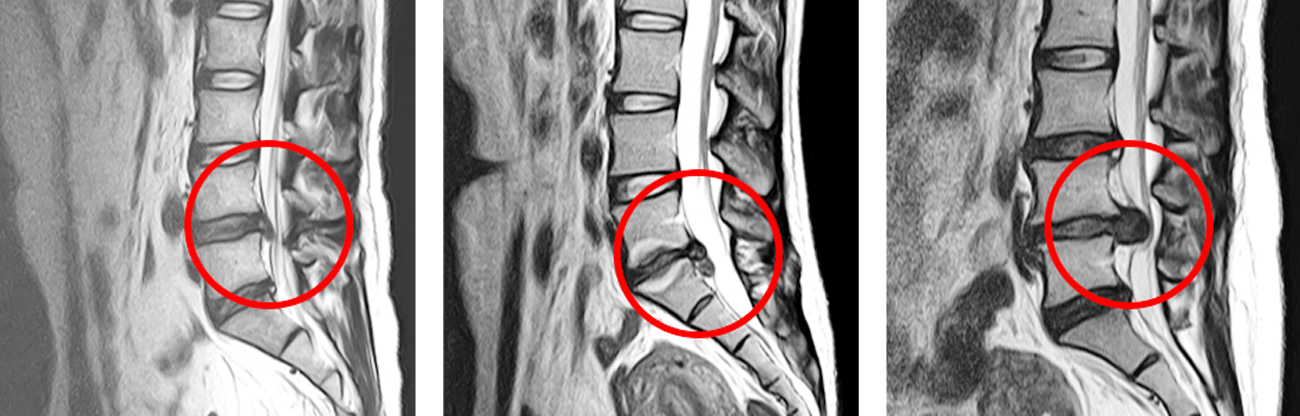

허리디스크 진단법

디스크나 단순한 요통 증상으로 판단하기 어려운 분들을 위해 집에서 할 수 있는 간단한 체크리스트를 알려드리겠습니다.

위의 다섯 가지 허리 디스크 진단 방법 중 두 가지 이상이 있는 경우 의사에게 문의하는 것이 좋습니다.